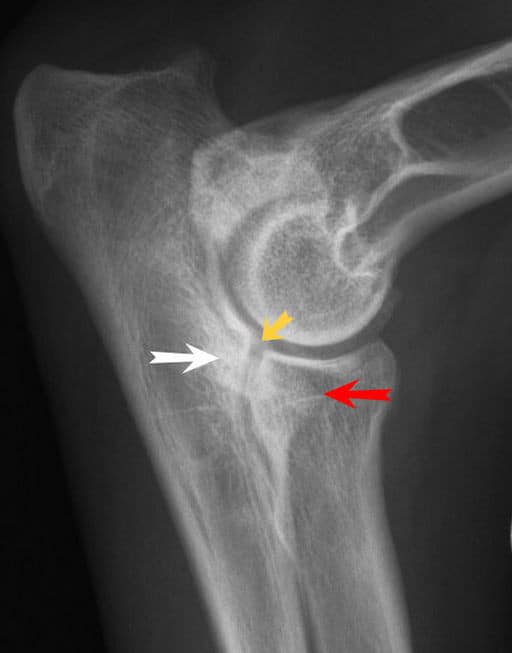

X-ray of canine elbow dysplasia, with arrows indicating defects in the joint.